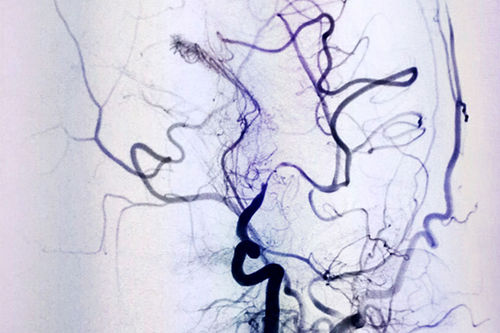

DSA血管介入诊断和治疗,像一种“血管艺术”,初看如水墨丹青一样的术中影像图,如同医护人员用智慧和技巧绘制的生命图谱。上海蓝十字脑科医院DSA血管介入诊疗是医院特色科室,拥有非常完善和先进的设备,李振并主任已经使用DSA成功诊断和治疗了很多大面积脑梗患者。

DSA血管造影,仿佛医生绘出的生命图腾

腔内血管成形术(球囊扩张支架置入术)是怎样治疗脑血管狭窄,从而大大减少大面积脑梗风险的呢?简单地说,是依据粗大导管通过狭窄血管时产生外向性压力,使血管腔扩大的原理,选择合适的球囊扩张支架,在DSA等影像设备的引导下,放置球囊扩张支架。该疗法可用于动脉、静脉、人造或移植血管,通过机械扩张导致血管重塑,可以提高血管开放率,治疗各种脑部狭窄性病变。